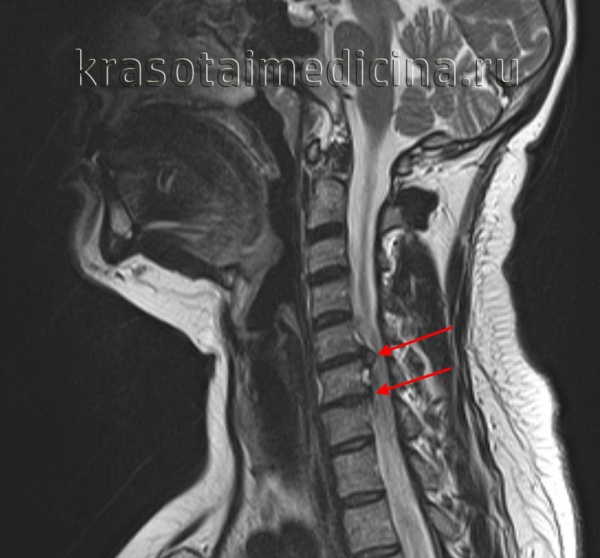

МРТ ШОП. Грыжевые выпячивания дисков в с. С5-С6, С6-С7 кзади, с выраженным сужением позвоночного канала и сдавлением спинного мозга.

МРТ ШОП. Грыжевые выпячивания дисков в с. С5-С6, С6-С7 кзади, с выраженным сужением позвоночного канала и сдавлением спинного мозга